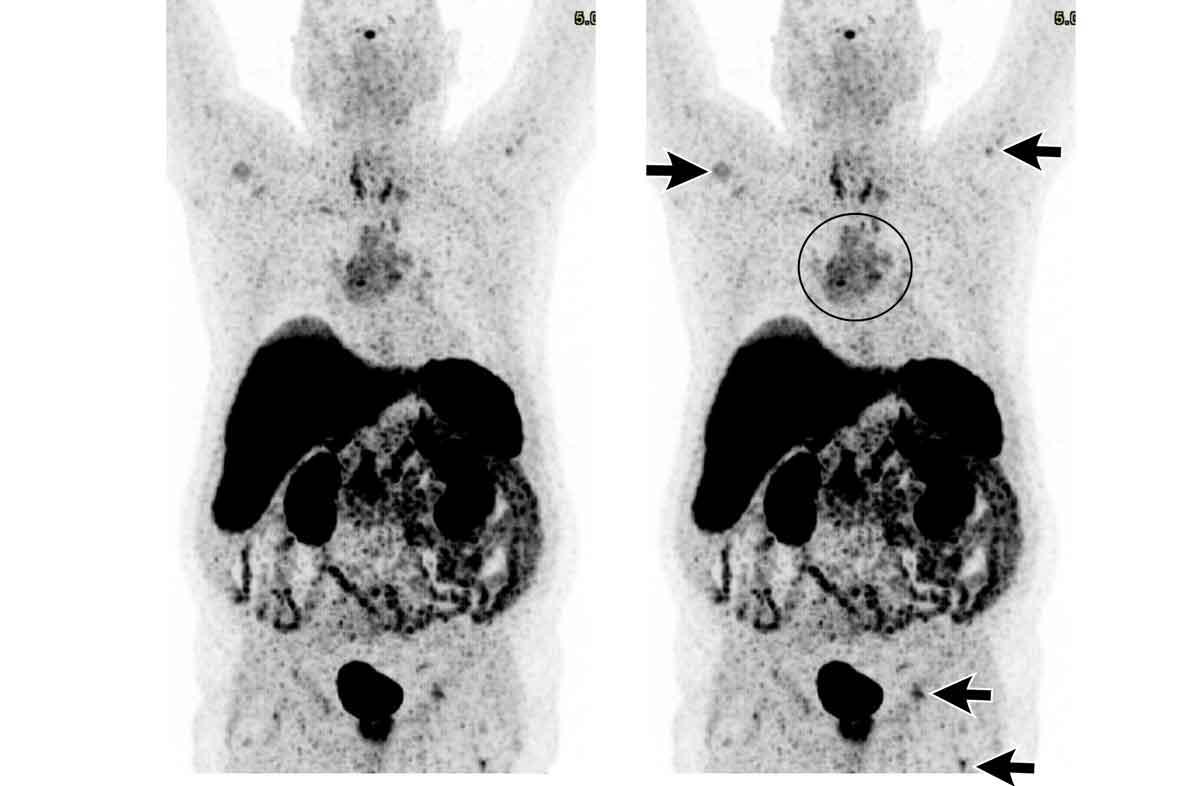

Các hình ảnh này của một bệnh nhân nam 36 tuổi bị hội chứng Cushing, đã được phẫu thuật cắt bỏ u tuyến yên.

Tuy nhiên, hội chứng Cushing vẫn tồn tại và phát hiện một khối ở trung thất.

Hình ảnh

Khối đặc với vôi hóa trung tâm (mũi tên đen).

Lưu ý bờ khối không đều ở phía bên trái.

Hạch bạch huyết thượng đòn trái to (hạch Virchow: mũi tên trắng).

Đây không phải là PET-CT thông thường mà là PET Dotatoc, được sử dụng để phát hiện u thần kinh nội tiết và các tổn thương di căn của chúng.

Có nhiều tổn thương di căn xương (mũi tên).

Chẩn đoán cuối cùng

U thần kinh nội tiết tuyến ức (NETT)